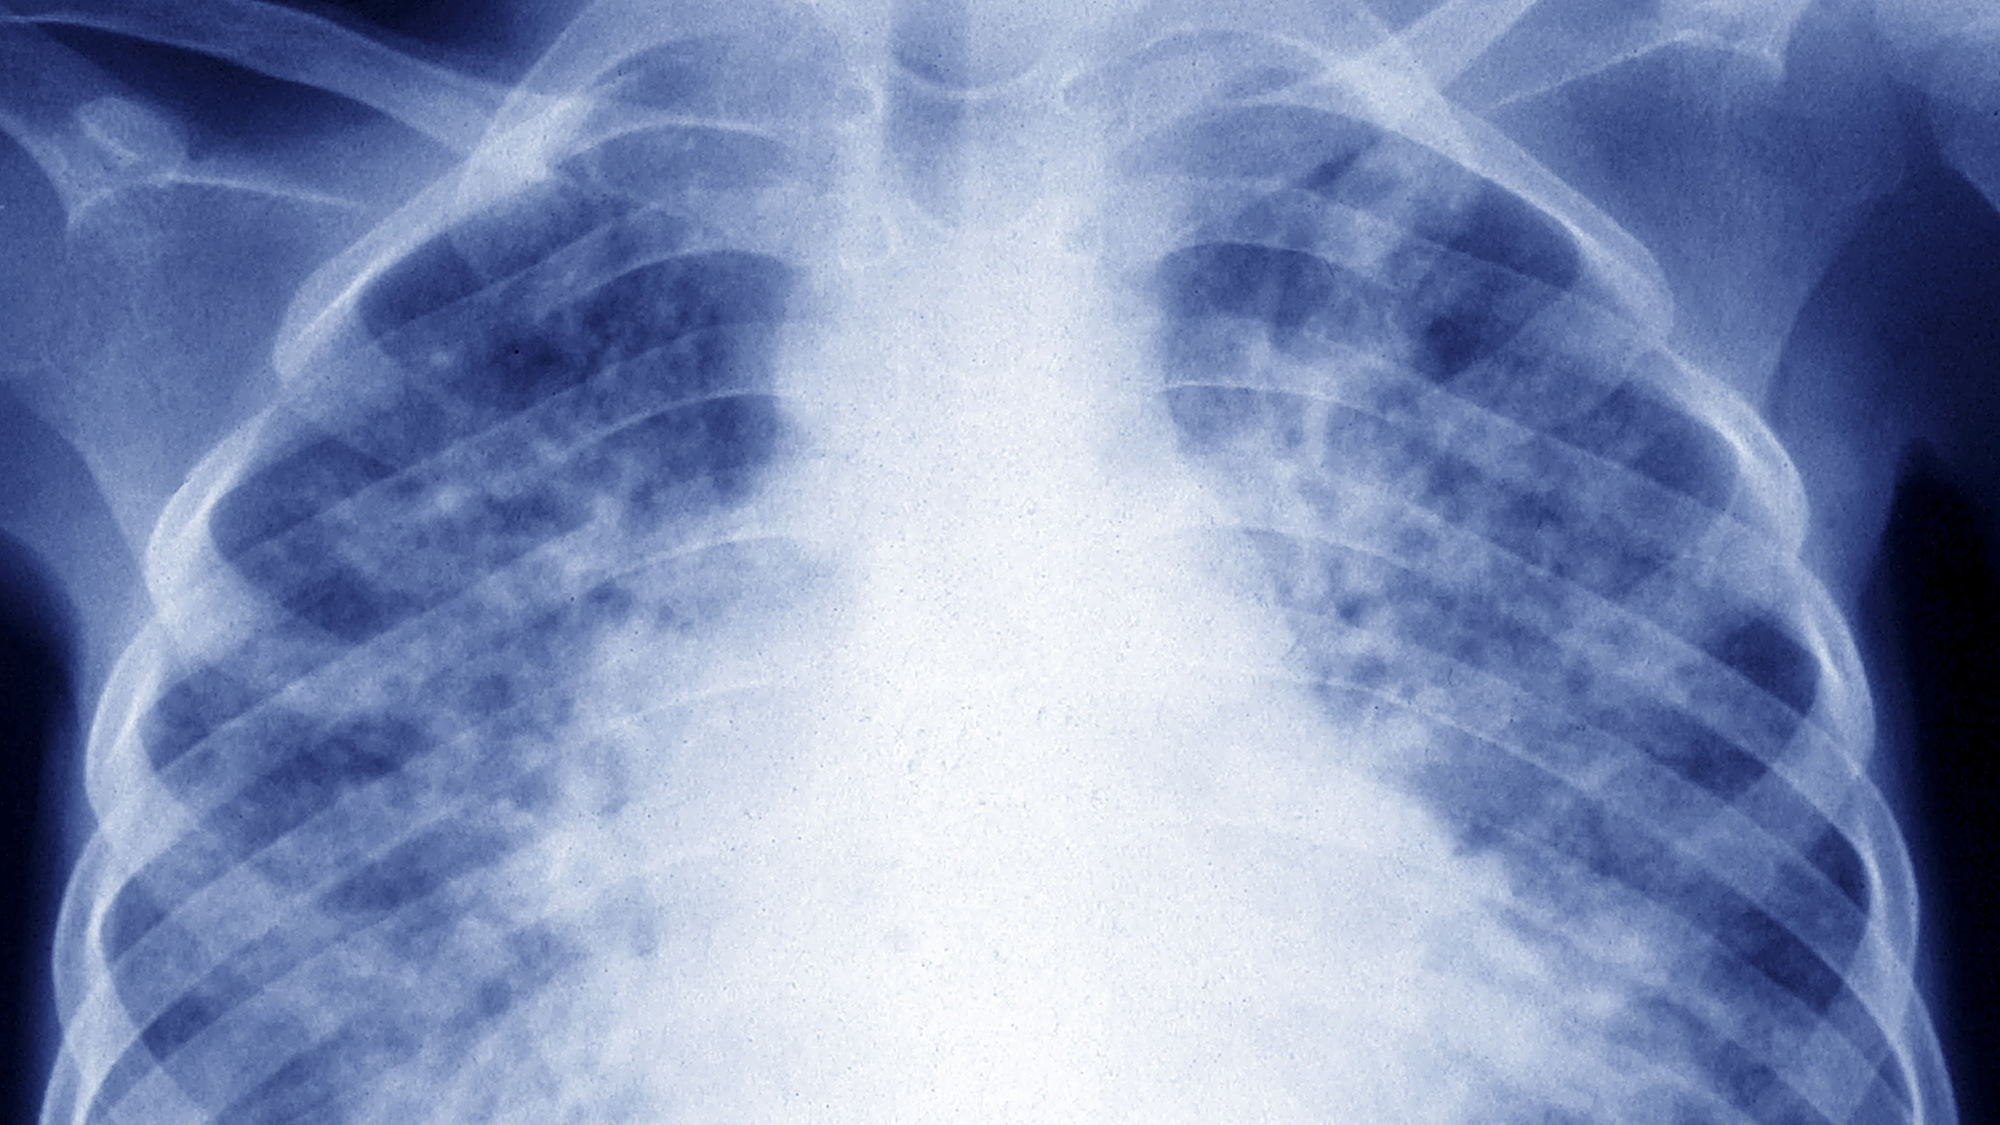

Pulmonary tuberculosis,spreading through the lungs.

Pulmonary tuberculosis,spreading through the lungs. BSIP/Universal Images Group via Getty Images